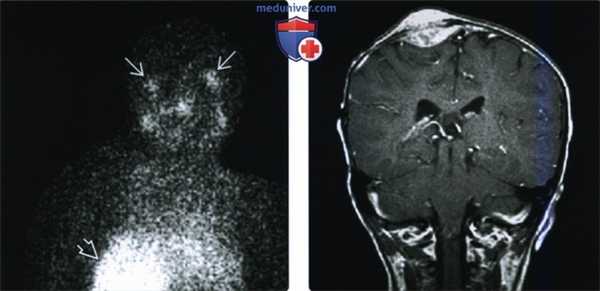

(Слева) При корональной сцинтиграмме с МИБГ, меченым йодом-123, определяются участки фиксации радиофармпрепарата в области глазниц, соотносящиеся с метастазами нейробластомы. Обратите внимание на большой участок гиперфиксации МИБГ в правой половине живота (первичная опухоль). Несмотря на то, что остеосцинтиграфия с МИБГ является высокоспецифичным методом диагностики нейробластных опухолей, до 30% первичных нейробластом и до 50% рецидивных нейробластных опухолей не фиксируют МИБГ.

(Справа) При корональной МРТ Т1ВИ С+ у ребенка с нейробластомой в диплоическом пространстве визуализируется образование с выбухающими краями. В опухоли можно выделить субпериостальный и эпидуральный компонент.